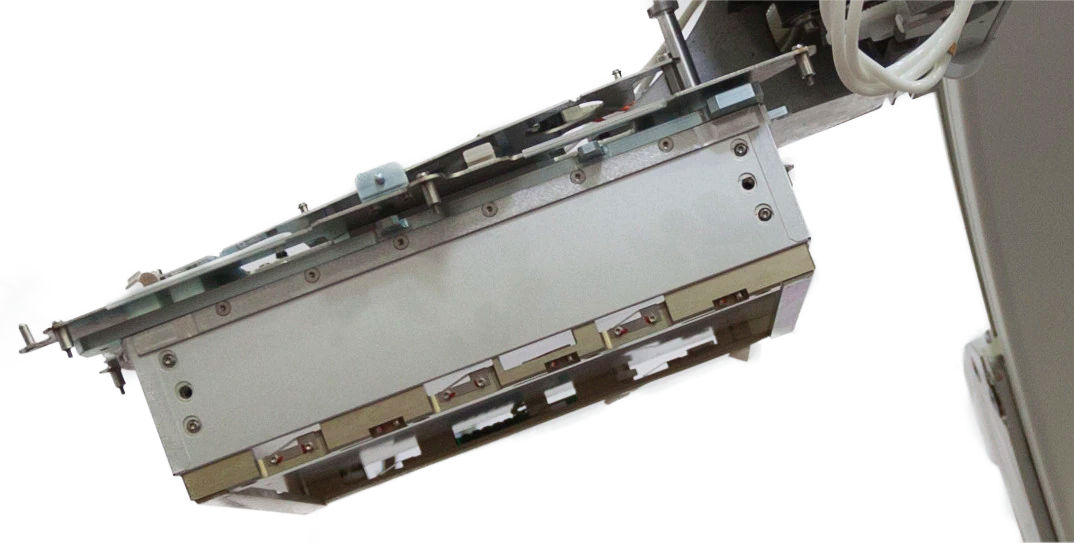

Exclusive design of the C-arm

Exclusive design of the C-arm